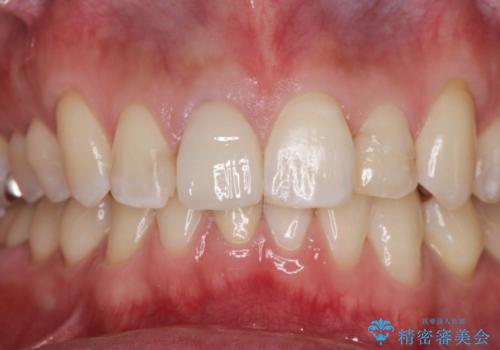

前歯の並びが改善し、色調の気になっていたクラウンの審美性も大きく改善することができました。